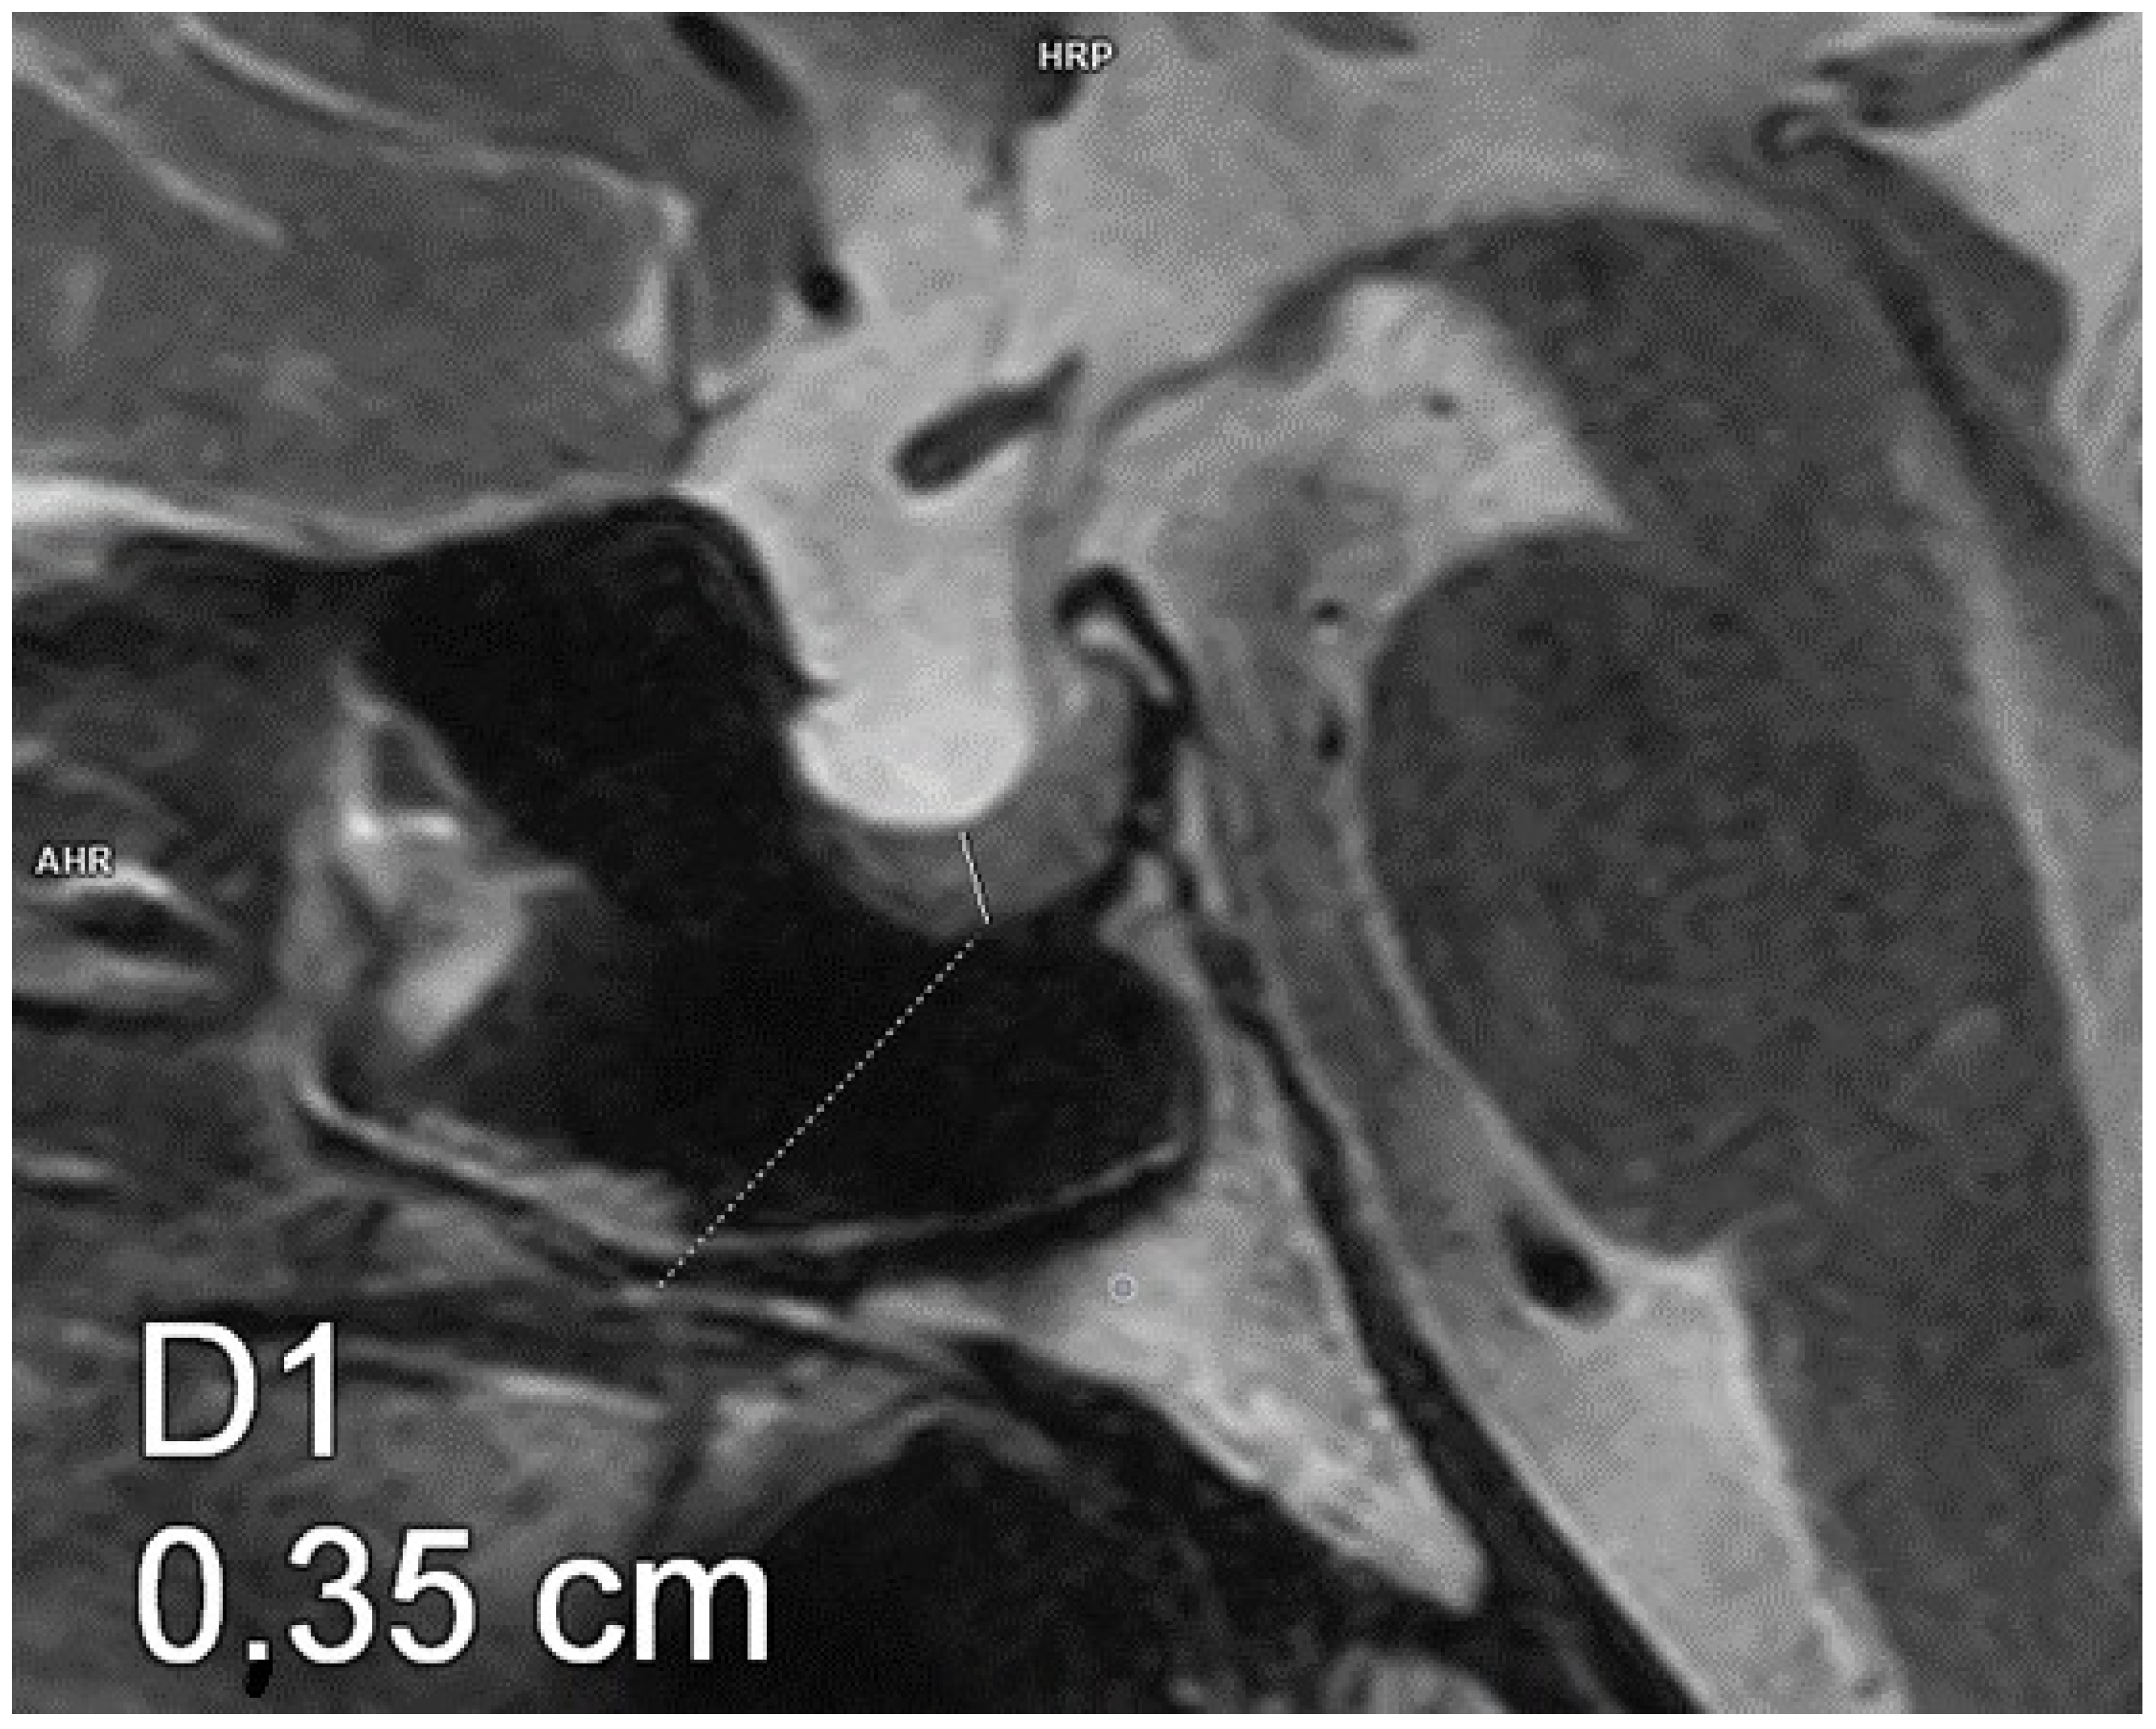

Figure 2.

Partial empty sella. Magnetic resonance imaging, T2-weighted image, sagittal plane. The craniocaudal diameter of the pituitary gland is 3.5 mm.